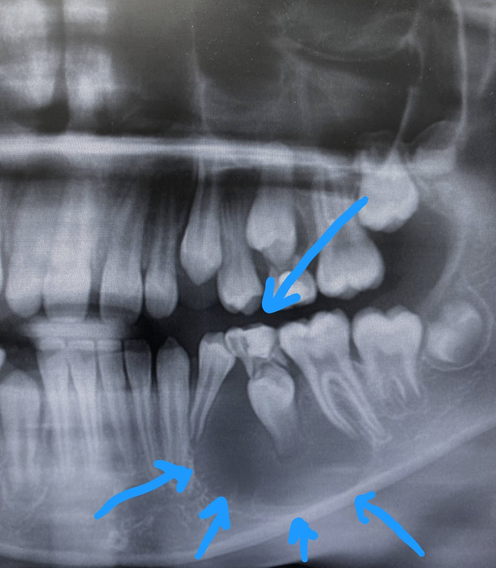

Вот другой пример коллег — это мостовидный протез с очень плохим состоянием тканей под ним:

Как видите, челюсть из-за отсутствия трофики тоже очень сильно истончилась. И пациент тоже уязвим к любому, даже довольно слабому удару. Морковку в отличие от прошлого примера ещё выдержит, потому что мост распределяет нагрузку на более широкие участки кости, а вот стоит быть чуточку неаккуратным — и приехали.

Чтобы вас не пугать лишний раз, на всякий пожарный отмечу, что этот случай редкий и характерен для очень малого количества мостов и пациентов. Обычно ткань кости уходит медленно, скорость такая, что опасность наступает далеко после окончания ожидаемого срока жизни пациента. Но здесь всё прошло куда быстрее.

Вот поэтому врачи и не любят мостовидных протезов: костная ткань под ними не работает. Если имплант даёт трофику, потому что на него идут постоянные нажатия, то здесь под мостом трофики нет. То, что вы видите, называется экстремальным истончением костной ткани.